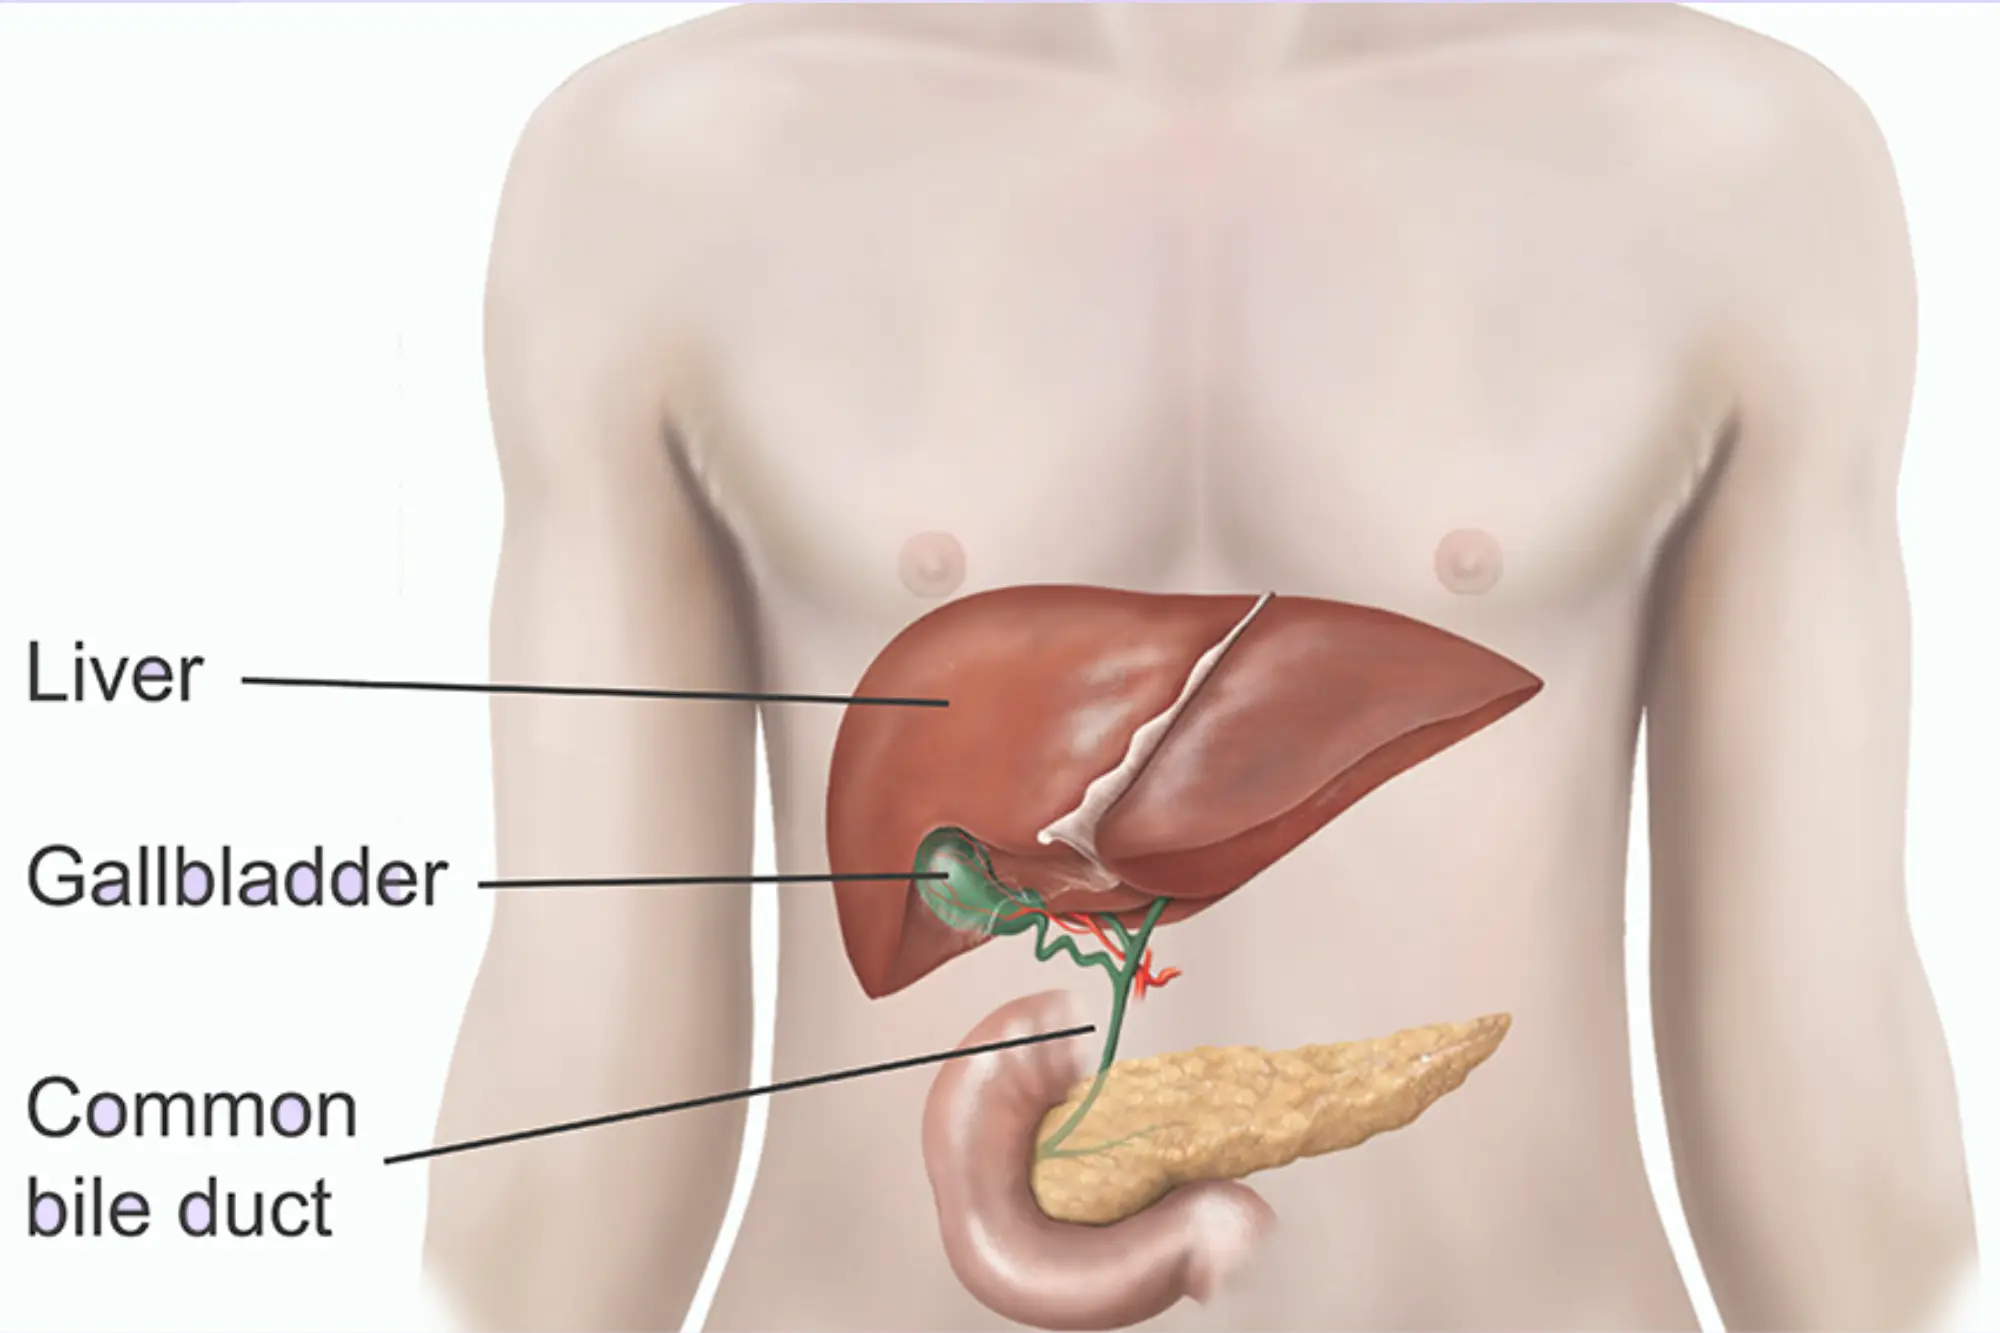

Open Cholecystectomy

Open Cholecystectomy is a surgical procedure to remove the gallbladder through a larger incision in the abdomen.